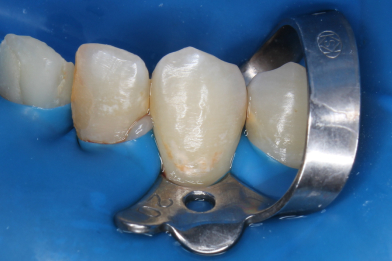

Выполнена изоляция рабочего поля. Под инфильтрационной анестезией раствором Артикаина 1:100000 1,7 мл. Препарирование кариозной полости зуба. Пломба Ceram•X™ светового отверждения. Анатомическая форма зуба и целостность контактного пункта восстановлены

Бояринов Сергей Эдуардович -